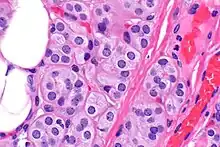

Microscopic image of a thyroid adenolipoma

Adenolipomas are diagnosed by surgical resection and examining the tumor with a microscope.[5] The presence of eccrine sweat glands are used to distinguish the tumor from a common lipoma. Size and the development of the capsule (tissue surrounding the tumor) can also aid in diagnosis. [6]